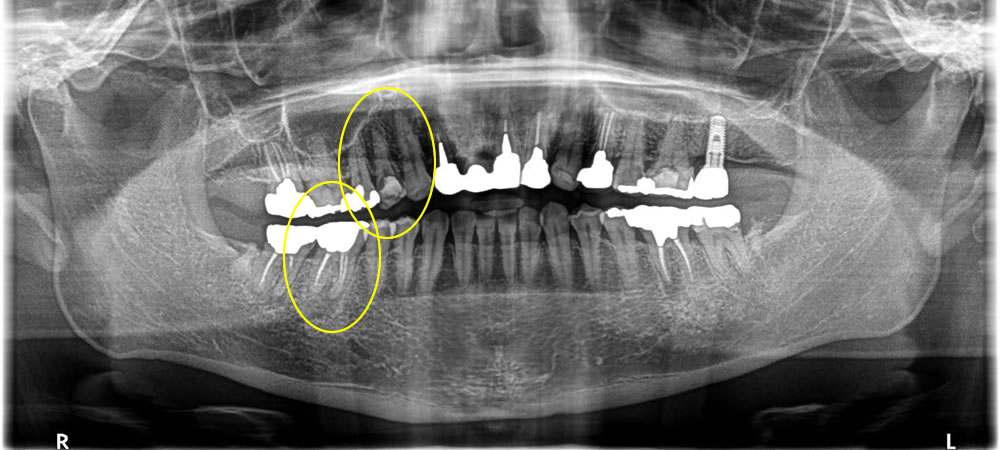

Before

| 年齢 | 40代 |

|---|---|

| 性別 | 男性 |

| 費用 | CT検査 0円 インプラント治療 (上部ジルコニア含め) 小臼歯 429,000円 骨造成 88,000円 大臼歯 407,000円 骨造成 110,000円 |

| 治療期間 | 4ヵ月 |

| 治療回数 | 4回 |